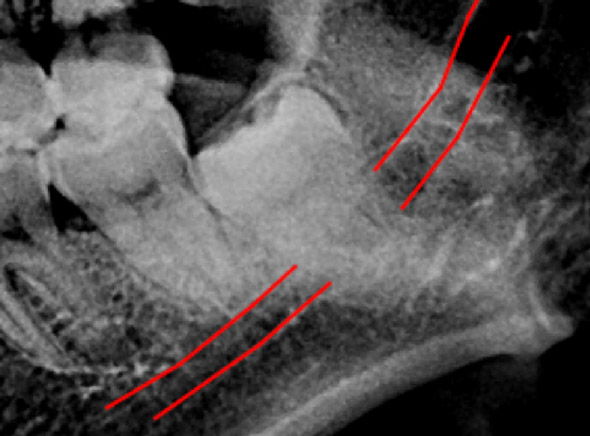

(兩條紅線中間黑色區域即為神經管)

外面拔時易斷裂於骨頭內而難以取出